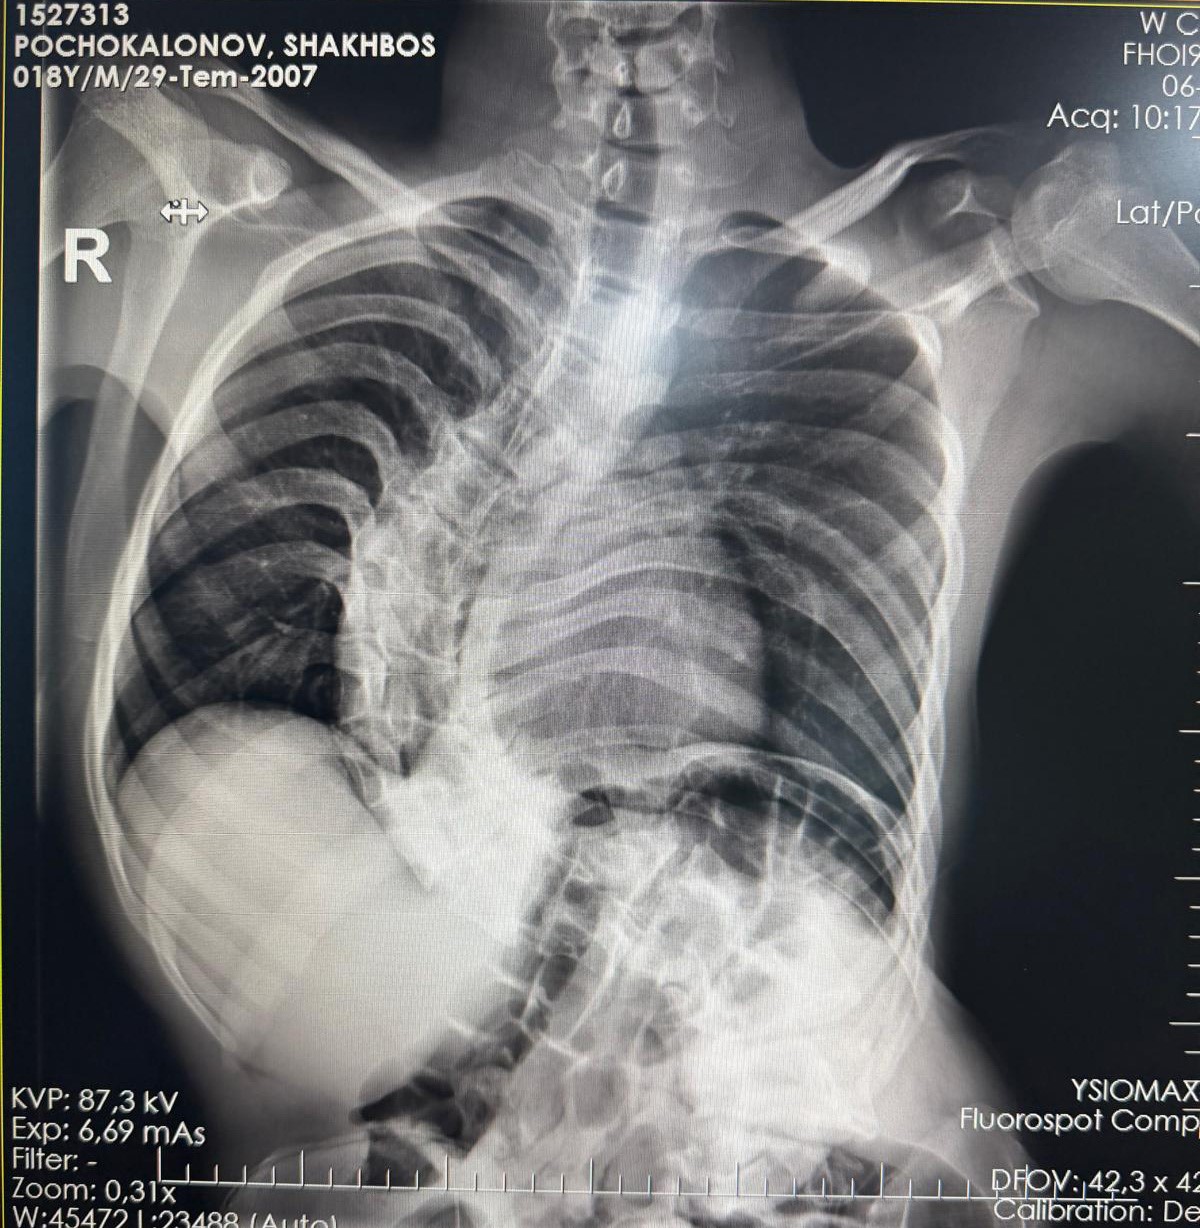

Başarılı geçen ameliyat sonrası hastanın yaşam kalitesinin önemli ölçüde arttığını belirten Ortopedi ve Travmatoloji uzmanı Prof. Dr. Mehmet Atıf Erol Aksekili, skolyoz hakkında bilgi vererek, "Skolyoz kısaca omurganın S şeklini almasıdır. Ön-arka planda omurganın S şeklini almasını biz kısaca skolyoz diyoruz. Skolyoz en sık adolesan dediğimiz ergenlik döneminde görülür. Ancak diğer hastalıklarla birlikte görüldüğünde daha ileri seviyelerde karşımıza çıkabilir. Hastamız 18 yaşında bize başvurdu. Nöromüsküler skolyoz dediğimiz, nörolojik hastalıkların eşlik ettiği bir skolyoz tipi mevcut. Bu skolyozlar erken yaşta ortaya çıkar ve daha hızlı ilerler. Bu yüzden hastamız bize 90 dereceden daha ileri bir seviyede başvurdu" dedi.

Erken teşhis edilmesi halinde daha az cerrahi ile daha iyi sonuç alınabileceğini belirten Aksekili, "Skolyoz erken tanındığında fizik tedavi, egzersiz ve korseleme gibi yöntemlerle ilerlemesini kontrol altına alabiliyoruz. Hastamızda ileri skolyoz olduğu için iki aşamalı cerrahi uygulandı. İlk aşamada Halo Femoral traksiyon yöntemiyle skolyoz kısmen düzeltildi. İkinci aşamada ise vidalar, rodlar ve osteotomi ile omurga düzeltildi" diye konuştu.